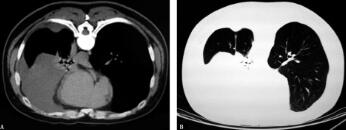

充分引流胸腔积液致左肺组织大部分复张,再次阅读胸部CT:左肺组织内未见异常病变,但左侧少许胸腔积液内靠近后胸壁处似见一局部密度增高影,呈梭形,故考虑有可能为胸腔积液原因。遂于2011年12月30日行俯卧位胸部CT(图3A纵隔窗、B肺窗)示左后胸壁胸膜局部增厚,可见一软组织密度影,呈梭形,大小约4.5cm×1.9cm,CT值约为35HU。故取得此软组织的病理,有可能真相大白。与家属沟通后,行CT引导下胸膜活检术。病理回报:透明细胞癌,免疫组化(图4 HE×40):Vimentin(+),CK(+),CD10(+),CK5/6(-),CR(-),MC(-),TTF(-),CK7(-),CEA(-),透明细胞癌,考虑肾细胞癌转移来源。

图3